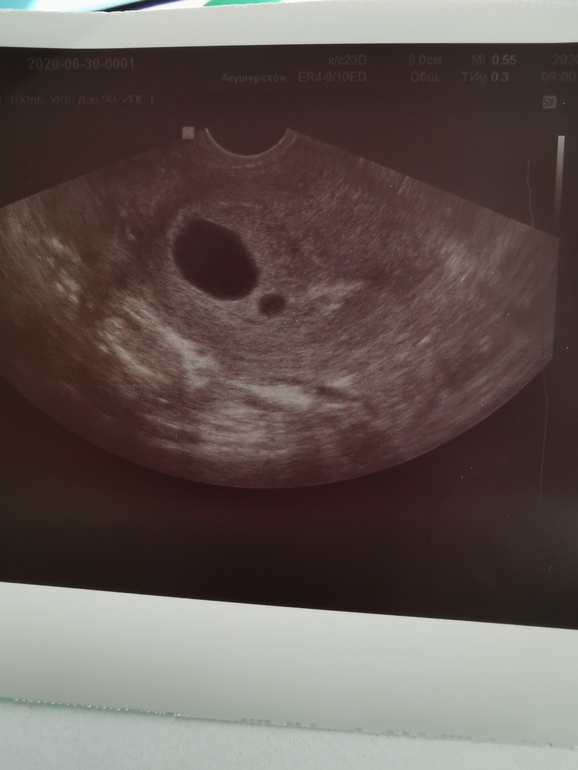

Вторая фаза 14? Вот точно вместе тогда пойдем :))). Сегодня на узи фолик был 20мм. Но тест на о пустой. Только прошлая у меня была в конце мая :)

27.06.2020

Ага, 14. Первая короткая У меня сегодня на УЗИ ДФ 23 и тесты полосатые). Так что 🤞🤞🤞

Значит прям сегодня может! 👍

Хоть бы, хоть бы). И вам скорейших двух полосок. Я там запрос в друзья отправила, чтобы не теряться 👍

Еще вчера подтвердила :)

28.06.2020